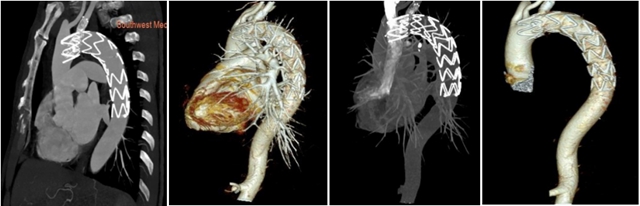

术后检查

这个真实案例强调了胸痛的凶险性、致命性以及一站式CT检查在及时诊断和治疗方面的不可或缺性。

胸痛三联征“一站式”CT检查是指通过一次扫描、一次注射造影剂可同时显示冠状动脉、肺动脉及主动脉三种血管的图像,有助于早期、快速诊断,同时可以最大程度降低辐射剂量。因此已成为目前评估急性胸痛患者的首选检查方法。

2.主动脉夹层的检测:这一检查能够清楚地显示主动脉的解剖结构,帮助医生观察主动脉夹层并确定其位置和严重程度,及时进行干预。